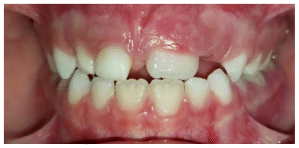

The patient was a growing female child who presented during early mixed dentition with an anterior crossbite associated with a deep overbite and a marked sagittal discrepancy (Figures 12–19). The initial clinical examination revealed a negative overjet, complete anterior deep bite, and a functional Class III occlusal pattern. Extraoral assessment showed a flattened facial profile, while cephalometric analysis confirmed a skeletal imbalance characterized by increased SNA and SNB values, an ANB of 0°, negative Withs appraisal, and significant dentoalveolar compensations, including proclination of both upper and lower incisors (Table 3). The vertical pattern was predominantly hypodivergent, suggesting a high risk of unfavorable mandibular growth progression if left untreated. Given the patient’s young age and growth potential, an early interceptive treatment was planned to use the AMCOP® TC appliance, with the aim of correcting the anterior crossbite, improving neuromuscular balance, and guiding sagittal and vertical development during growth. The appliance was worn nightly and for additional daytime hours, according to patient compliance.

After 18 months of treatment, a clear clinical improvement was observed. Intraoral examination demonstrated complete correction of the anterior crossbite, with establishment of a positive overjet and normalization of the anterior occlusal relationship. The deep bite was reduced, allowing more functional anterior guidance. Occlusal relationships improved toward a stable dental Class I, and the need for excessive dentoalveolar compensation was reduced. Cephalometric reassessment showed an overall improvement in sagittal relationships and incisor inclinations, with a trend toward normalization of the previously altered parameters. These findings indicate that early functional therapy with the AMCOP® TC appliance was effective in intercepting the developing Class III malocclusion, improving occlusal function, and potentially reducing the severity of future skeletal discrepancies (Table 4).

This case highlights the importance of early diagnosis and timely functional intervention in growing patients, demonstrating how interceptive treatment can favorably influence occlusal development and facial balance during critical growth phases.